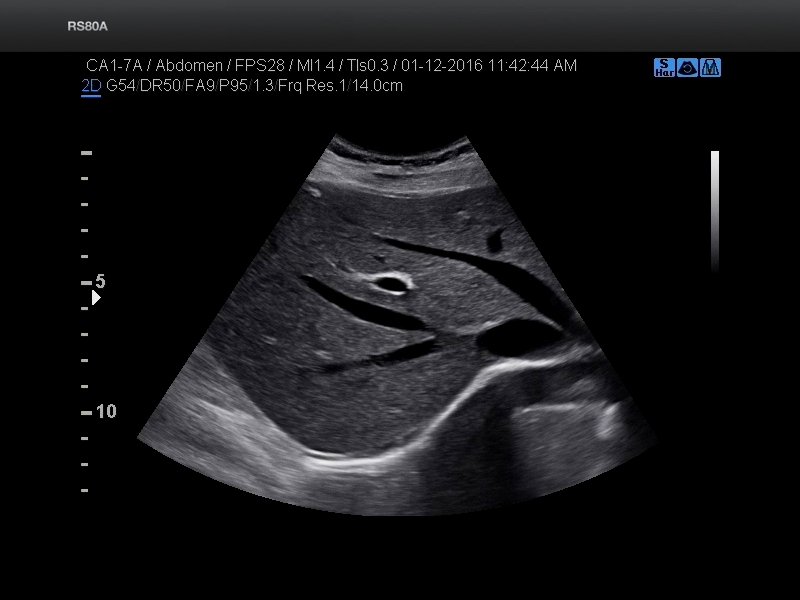

Liver, S-Harmonic (echogramm №692)

[RU] Ultrasound image №692: Liver in S-Harmonic mode.

Echogramm was received by ultrasound scanner RS80 (out of production).